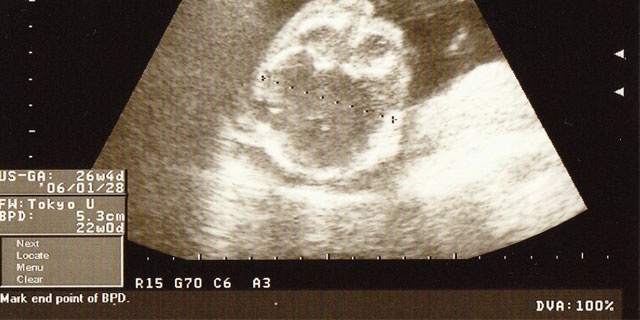

そこで今回は「妊娠6カ月とスポーツ選手の子育て論」について、医師に解説をしていただきました。妊娠6カ月の胎児の状態

個人差はありますが、妊娠20週くらいで200㎜前後であることが多いです。

赤ちゃんの体重

体重も個人差がありますが、妊娠20週で200g台の前半から300g台の半ばまでというのが一般的です。

赤ちゃんの機能

大体の主だった器官が出来上がり、形も生まれるときと似通った形になっています。耳も聞こえるようになってきている場合もあります。

性別

健診時の赤ちゃんの体の向きなどにもよりますが、わかるようになっていることが多いでしょう。 妊娠6カ月付近のお母さんの様子